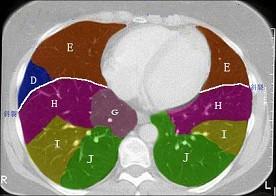

结合肺段模式(见图),选出右肺下叶的组成 ( )A、F+G+H+IB、F+G+H+I+JC、F+GD、F+G+HE、F

问题 结合肺段模式(见图),选出右肺下叶的组成 ( )

选项 A、F+G+H+I B、F+G+H+I+J C、F+G D、F+G+H E、F

答案 B